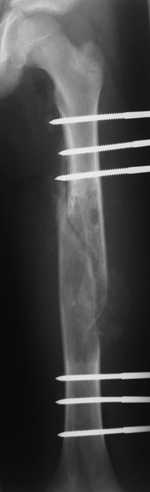

[Ortho] Pathological fracture femur

Most likely fibrous dysplasia, we had the same case but younger age

patient 4 years ago treated by uniplanar ext fix followed by percut.

curretage and bone marrow injection and healed well.

at this age IMN can solve the problem .